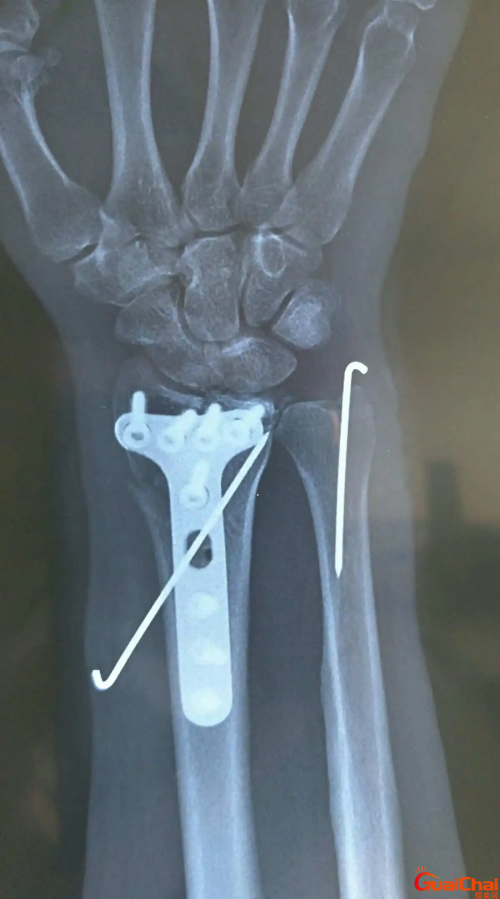

桡骨是身体的哪个部位?桡骨是什么部位?桡骨(radius)位于前臂外侧部,分一体两端。上端膨大称桡骨头head of radius,头上面的关节凹与肱骨小头相关节;周围的环状关节面与尺骨相关节;头下方略细,称桡骨颈(neck of radiusa)颈的内下侧有突起的桡骨粗隆(radial tuberosity)桡骨体呈二棱柱形,内侧缘为薄锐的骨间缘。下端前凹后凸,外侧向下突出,称茎突(styloid processo),下端内面有关节面,称尺切迹,与尺骨头相关节,下面有腕关节面与腕骨相关节。桡骨茎突和桡骨头在体表可扪到。人跌倒手过伸着地时,间接暴力可引起桡骨小头骨折或下端骨折(colles)骨折。